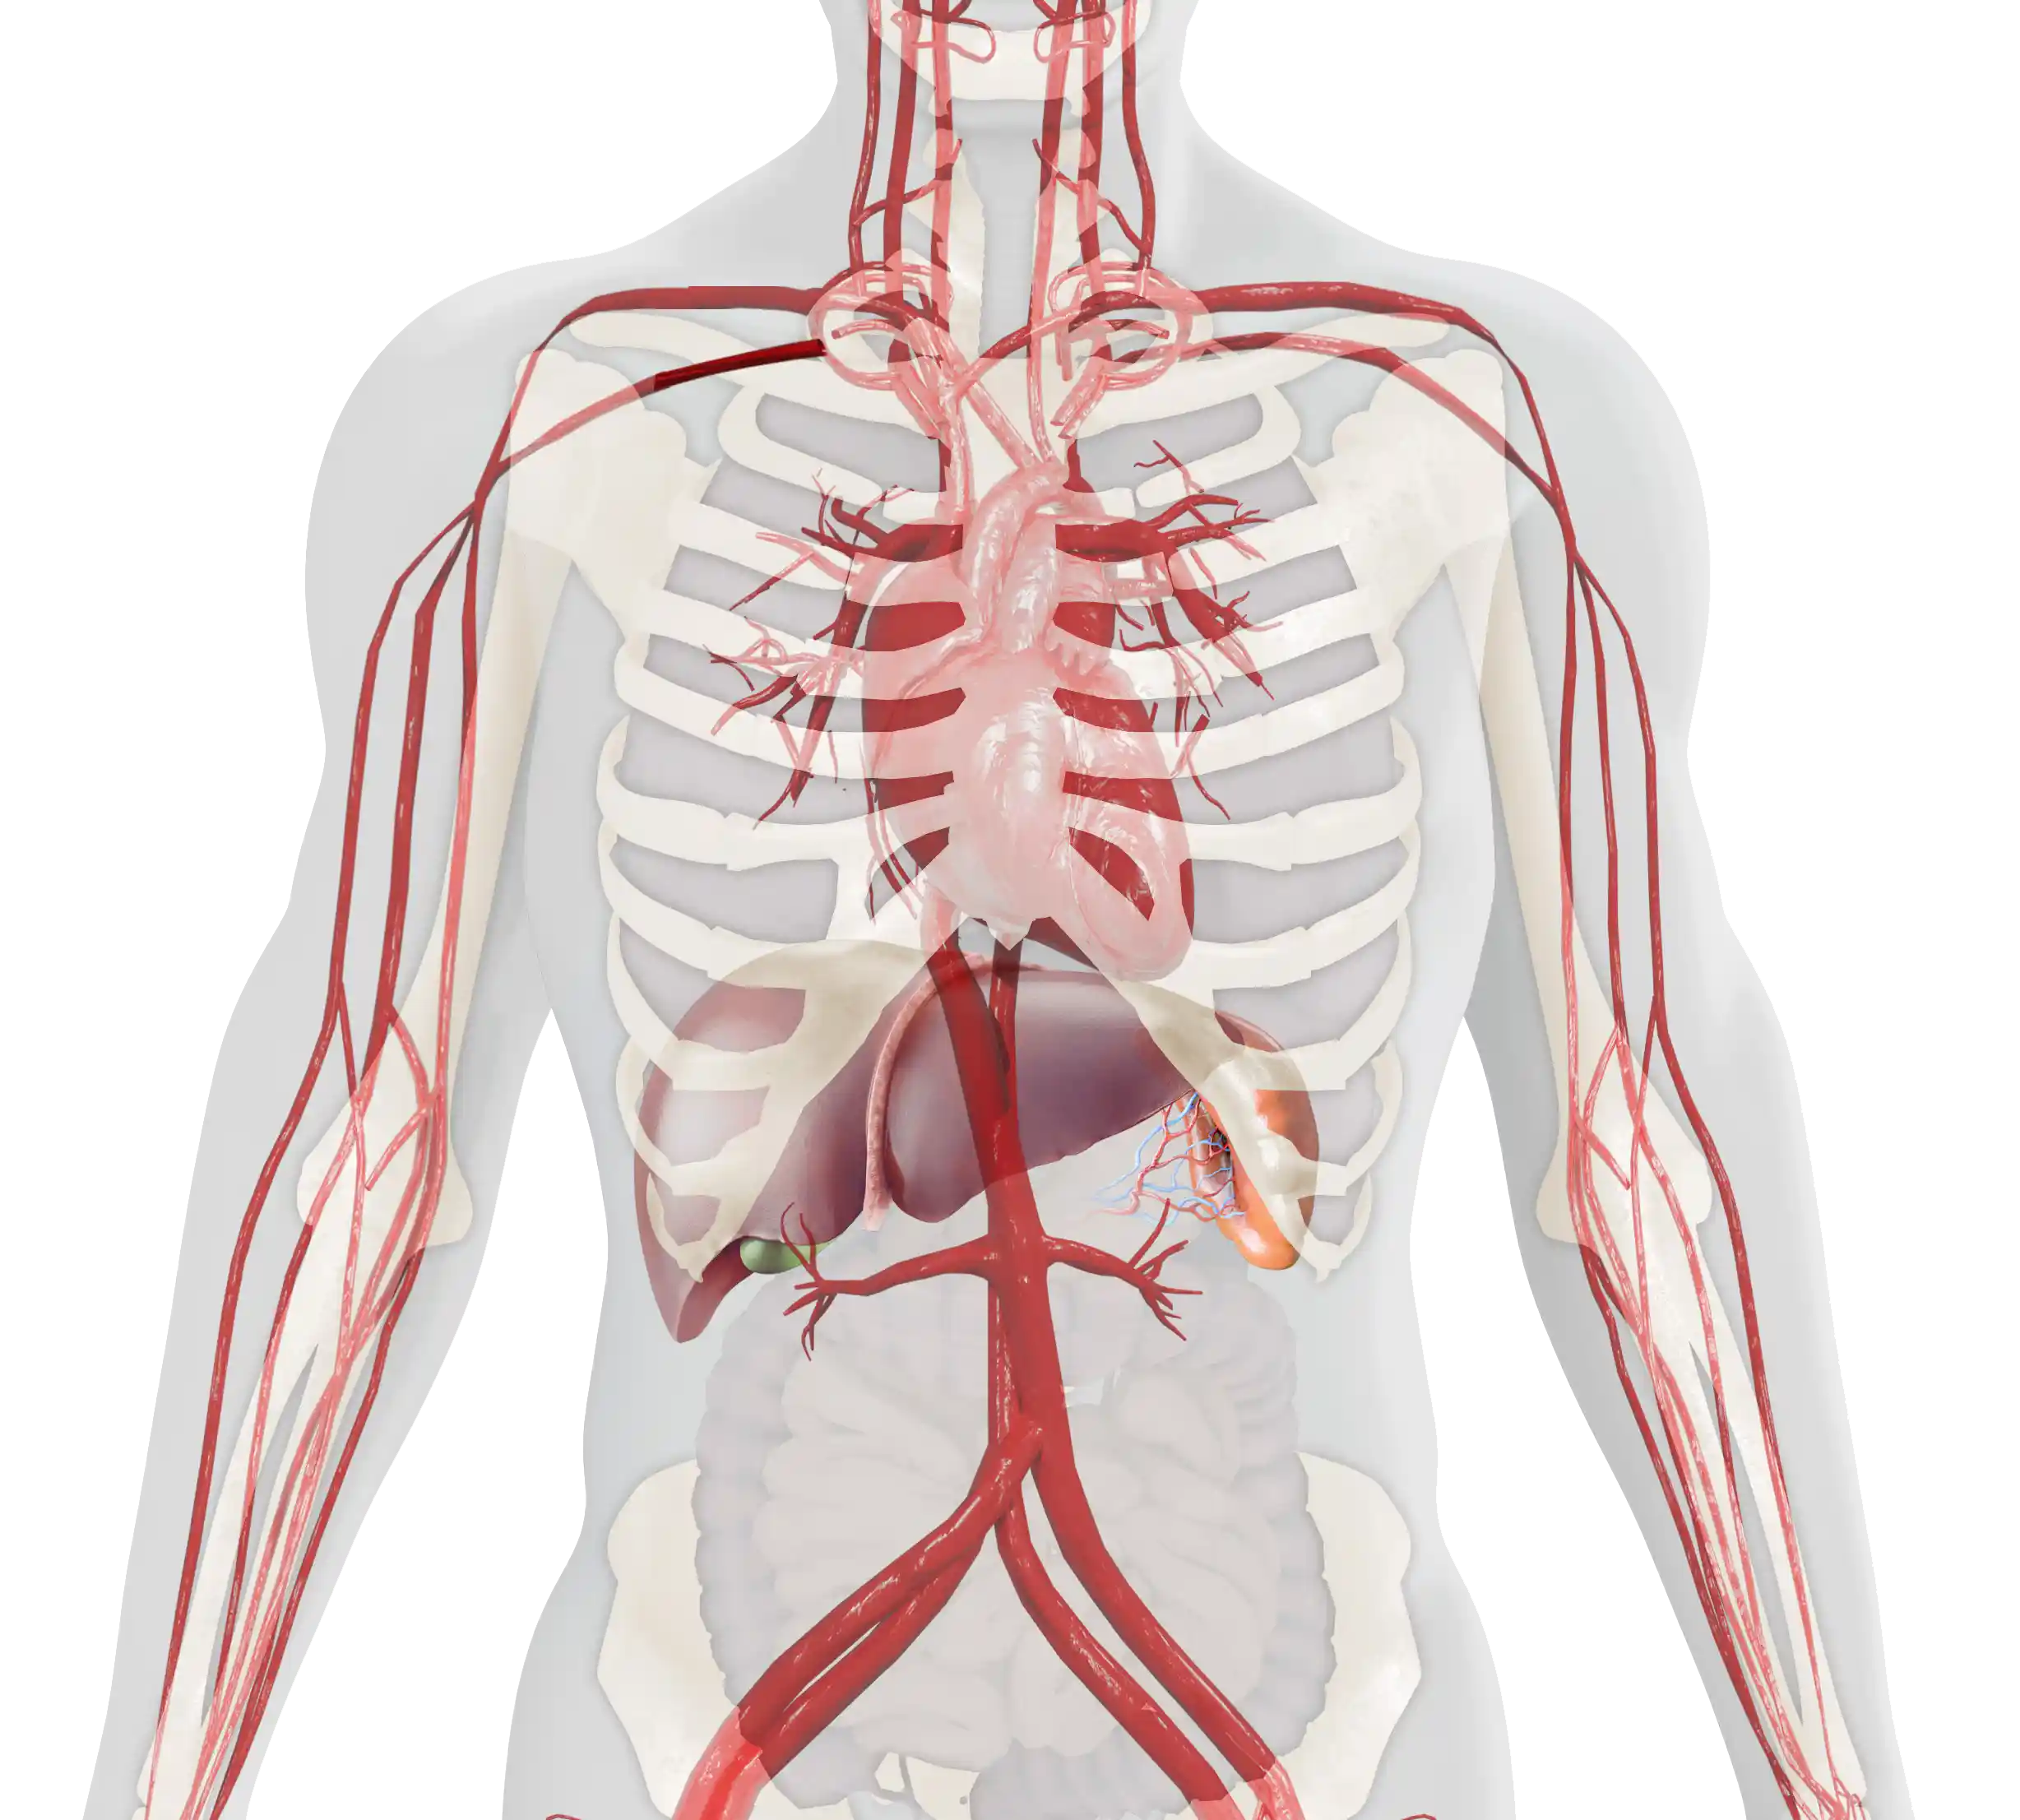

Patients with GD have a deficiency of the enzyme glucocerebrosidase, the enzyme responsible for catalyzing glucocerebroside.1–3 The progressive accumulation of glucocerebroside throughout the body leads to a variety of symptoms that present in various organs.1,4–6

Gaucher disease (GD) is a rare, autosomal recessive lysosomal storage disorder, in which deficiency of the enzyme glucocerebrosidase leads to the accumulation of its substrate glucocerebroside throughout the body, primarily in the spleen, liver, and bone marrow.1–3 The accumulation of glucocerebroside in the different areas of the body leads to the progressive, multi-systemic, and heterogeneous nature of the disease.1,4

- Gaucher cells infiltrate organs and tissues enriched in cells of the mononuclear phagocyte system, e.g., the spleen, liver, and bone marrow.1,9,10

- Over time, they displace normal cells resulting in progressive impairment; the liver and spleen may become enlarged, which can interfere with normal functioning and cause a painful and swollen abdomen.1,8,9,11

Splenomegaly occurs in 95% of patients with GD1. It may be one of the first and most physically prominent presentations of GD1 in patients. Splenomegaly results in abdominal distension and early satiety.4–7 Many patients complain of acute abdominal pain, which can be worsened by splenic infarction.1,8

Enlargement of the liver occurs in 80% of patients with GD1, also contributing to abdominal pain and early satiety.1,5,7 Hepatomegaly may progress to liver disease and cirrhosis.1,4